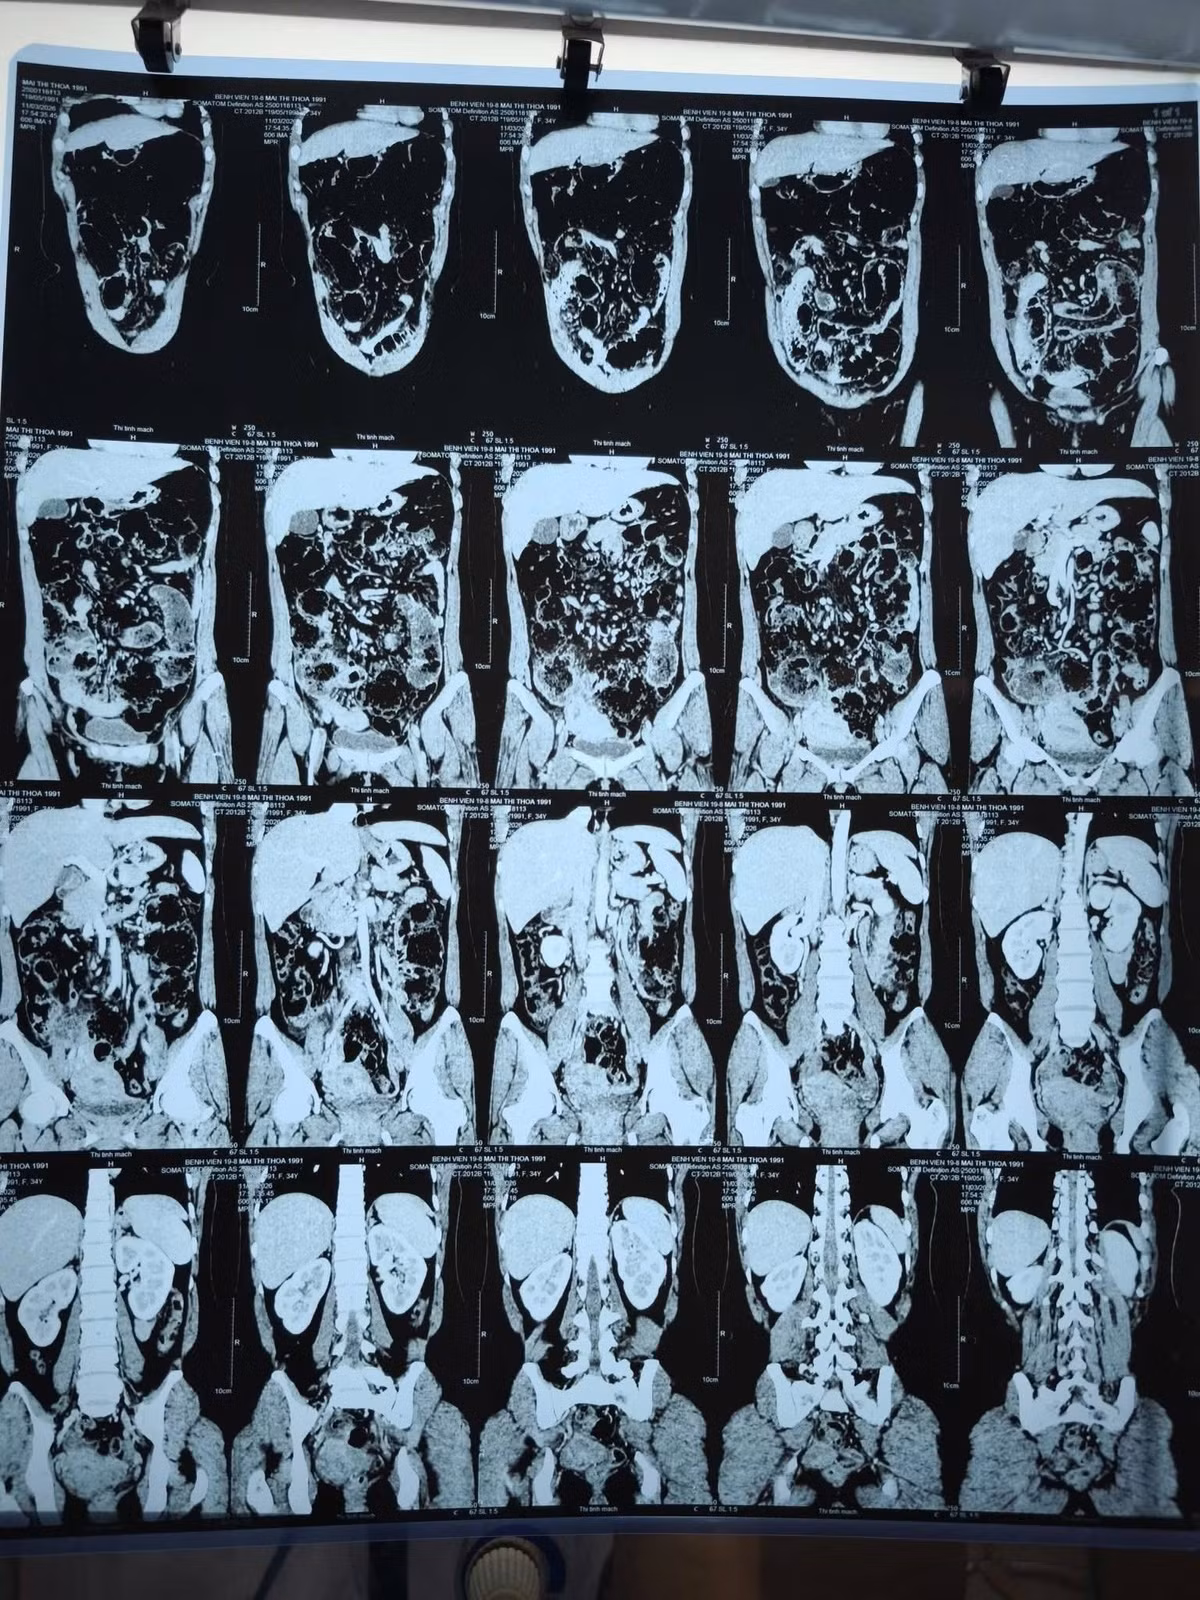

da-tui-thua1.jpg

Hình ảnh đa túi thừa trên phim chụp - Ảnh BVCC

Kết quả chẩn đoán ban đầu qua CT Scanner gây nhầm lẫn với tắc ruột do bã thức ăn. Đây là một "cái bẫy" hình ảnh học phổ biến vì túi thừa chứa phân non rất dễ bị nhầm với khối bã thức ăn.

da-tui-thua-2.jpg

Chẩn đoán hình ảnh CT Scanner là công cụ quan trọng nhất để phát hiện đa túi thừa - Ảnh BVCC

Đa túi thừa ruột non (JID) không chỉ ở người già: Dù tỷ lệ lưu hành chỉ từ 0,1% - 1,5%, bệnh vẫn có thể xuất hiện ở người trẻ tuổi với các biến chứng nguy hiểm như thủng, chảy máu tiêu hóa hoặc tắc ruột.

Chẩn đoán hình ảnh CT Scanner là công cụ quan trọng nhất, nhưng cần sự phân tích tỉ mỉ từ bác sĩ để phân biệt túi thừa với các nguyên nhân tắc ruột khác.